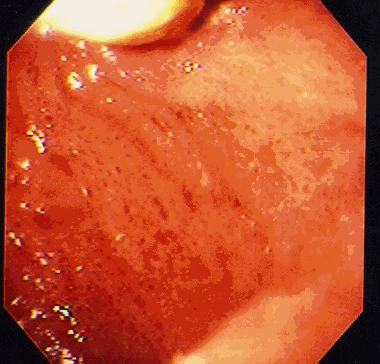

As alterações da gastropatia hipertensiva portal são mais evidentes na mucosa do corpo e fundo do estômago. Os aspectos endoscópicos incluem um padrão de eritema fino, difuso e pontilhado, rash escarlatiniforme ou o padrão conhecido como “pele de cobra” ou “mosaico”, onde se observa áreas avermelhadas, pequenas e poligonais delimitadas por bordas deprimidas e amarelo claras5-8. A gastropatia severa é caracterizada pela presença de pontos vermelho escuros ( “cherry red spots” ) e áreas de hemorragia mucosa difusa ( “gastrite hemorrágica” )5,8. Em estudos endoscópicos com grande amostragem de cirróticos assintomáticos, mais que 50 % apresentam sinais de gastropatia hipertensiva portal, sendo o achado mais comum o padrão mosaico ou em pele de cobra no estômago proximal8,9.

Em 1994, o NIEC (New Italian Endoscopic Club) propôs nova classificação para padronizar as descrições da gastropatia hipertensiva portal10. A classificação se baseia em 4 sinais endoscópicos elementares (tabela 2).

| Classificação da gastropatia hipertensiva portal (Milão –1994) |

| 1. Padrão mosaico ( mosaic-like pattern – MLP ), graduado como leve, moderado ou severo |

| 2. Marcas vermelhas ( red marks – RM ), que incluem lesões puntiformes vermelhas ( red point lesions – RPL ) e pontos vermelho cereja ( cherry red spots – CRS ) |

| 3. Pontos marrom escuros ( black Brown spots – BBS ) |

TRATAMENTO